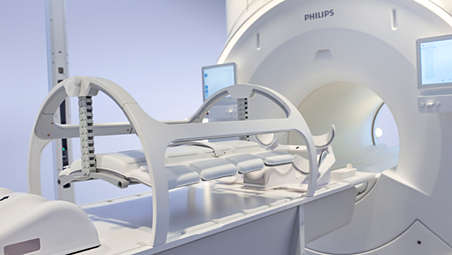

Whether for external beam radiation therapy (RT) or brachytherapy, integrating MR imaging into CT‑based planning can harness the power of MRI and transform patient management. With MRI’s excellent soft-tissue contrast, you can clearly see the tumor and organs at risk. So you can support accuracy in delineation and design the best possible treatment plans. Image courtesy of William Beaumont Health System, Detroit, USA - A superb MRI platform for radiation oncology

Ingenia MR-RT drives clinical excellence with state-of-the art image quality and high geometric accuracy thanks to dStream architecture, high gradient linearity, and 3D Gradient Distortion Correction. With the state-of-the art next generation Elition 3.0T and Ambition 1.5T wide-bore MR systems, you can benefit from MRI innovations, now and in years to come. - Maintain high standards

Position with precision

Highly-targeted RT plans rely on reproducible patient positioning in the treatment position. Unique to Philips, the integrated MR-RT CouchTop frees up in-bore space while improving SNR by bringing patients closer to the posterior coil*. Complete with indexing, the CouchTop accommodates a variety of MRI-compatible immobilization accessories from main vendors. - Work your way

Set up easily and flexibly

The Anterior Coil Support enables easy and flexible coil setup with large bore access and space for patient immobilization. The support can be easily tilted by a single operator to bring the coil close to the patient to optimize SNR without touching the body’s contours. - MR-linac simulation package for Elekta Unity

Whether for external beam radiation therapy (RT) or brachytherapy, integrating MR imaging into CT‑based planning can harness the power of MRI and transform patient management. With MRI’s excellent soft-tissue contrast, you can clearly see the tumor and organs at risk. So you can support accuracy in delineation and design the best possible treatment plans. Image courtesy of William Beaumont Health System, Detroit, USA - A superb MRI platform for radiation oncology

Ingenia MR-RT drives clinical excellence with state-of-the art image quality and high geometric accuracy thanks to dStream architecture, high gradient linearity, and 3D Gradient Distortion Correction. With the state-of-the art next generation Elition 3.0T and Ambition 1.5T wide-bore MR systems, you can benefit from MRI innovations, now and in years to come. - Maintain high standards

Highly-targeted RT plans rely on reproducible patient positioning in the treatment position. Unique to Philips, the integrated MR-RT CouchTop frees up in-bore space while improving SNR by bringing patients closer to the posterior coil*. Complete with indexing, the CouchTop accommodates a variety of MRI-compatible immobilization accessories from main vendors. - Work your way

A superb MR platform for radiation oncology

Ingenia MR-RT drives clinical excellence with

state-of-the art image quality and high geometric accuracy thanks to dStream architecture, high gradient linearity, and 3D Gradient Distortion Correction. With thestate-of-the art next generationElition 3.0T and Ambition 1.5T wide-bore MR systems, you can benefit from MRI innovations, now and in years to come.